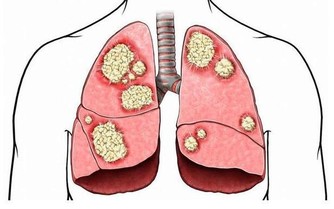

東南大學附屬中大醫院中醫骨傷科主任屈留新解釋,腳踝部位分布著淋巴管、血管、神經等近十個重要的組織,被稱為人體的第二心臟,如果經常把腳踝露出來,不僅會引發踝關節炎,還會使抗病能力下降而導致感冒。

另外,東南大學附屬中大醫院中醫骨科副主任醫師陸軍說,腳踝承受著全身的重量,是人體比較脆弱的地方,對外傷缺乏緩衝,很容易受到各種傷害。再加上踝關節周圍軟組織少,局部血液循環較差,如果再不穿襪子加以保護,很容易著涼而引發疾病。而能不能露腳踝,還要看個人體質,不要盲目去效仿。